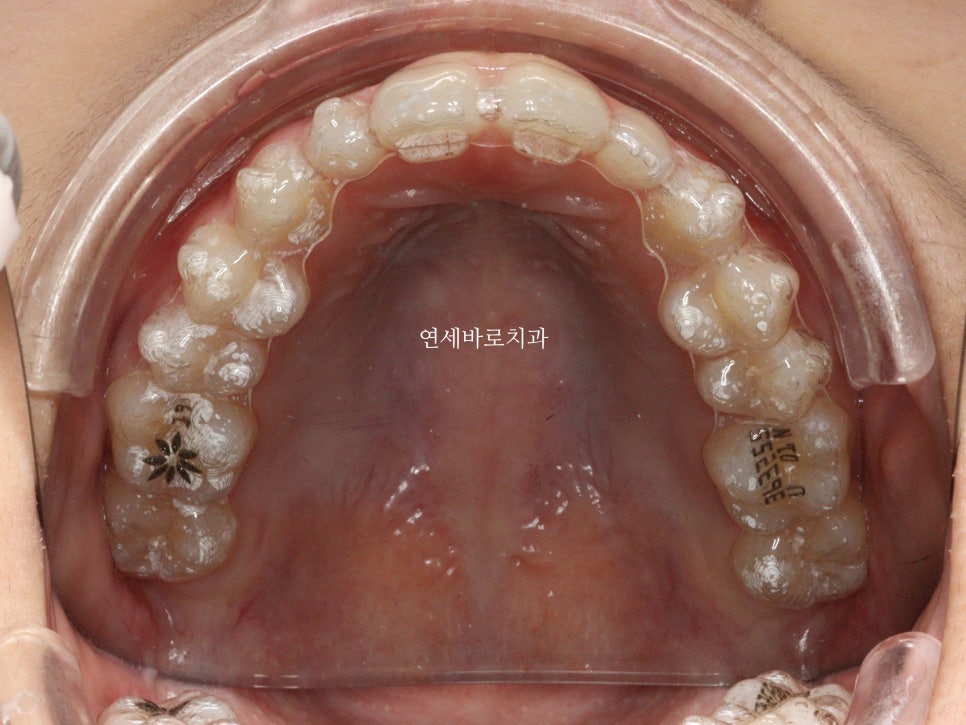

1월에 왔던 아이입니다. 어금니 교합은 너무나 좋아서 건들일것이 없었어요

앞니만 부분교정으로도 충분했습니다.

처음 치료를 시작한 날의 모습입니다.